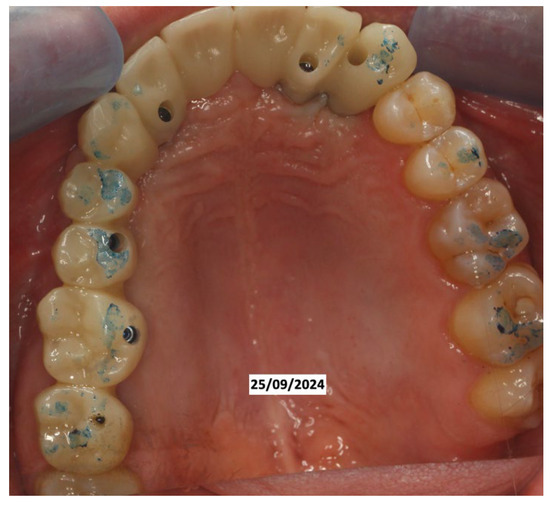

In June 2024, the implants were inserted in areas 16 and 17. Three months after the insertion of the last implants in 16-17 (4.2 × 10 mm and 4.2 × 8 mm, Biotech Dental, Allée de Craponne, Salon de Provence, France), it was possible to proceed with the digital impression-taking to proceed with a temporary prosthesis in PMMA (Figure 9) after a radiographic control (Figure 10).

The case has now been finalized, and the radiographic follow-up shows a stability of the bone regenerations obtained (Figure 11), with no new external root resorptions on the residual teeth.

Figure 9. Fixed prosthetic rehabilitation.